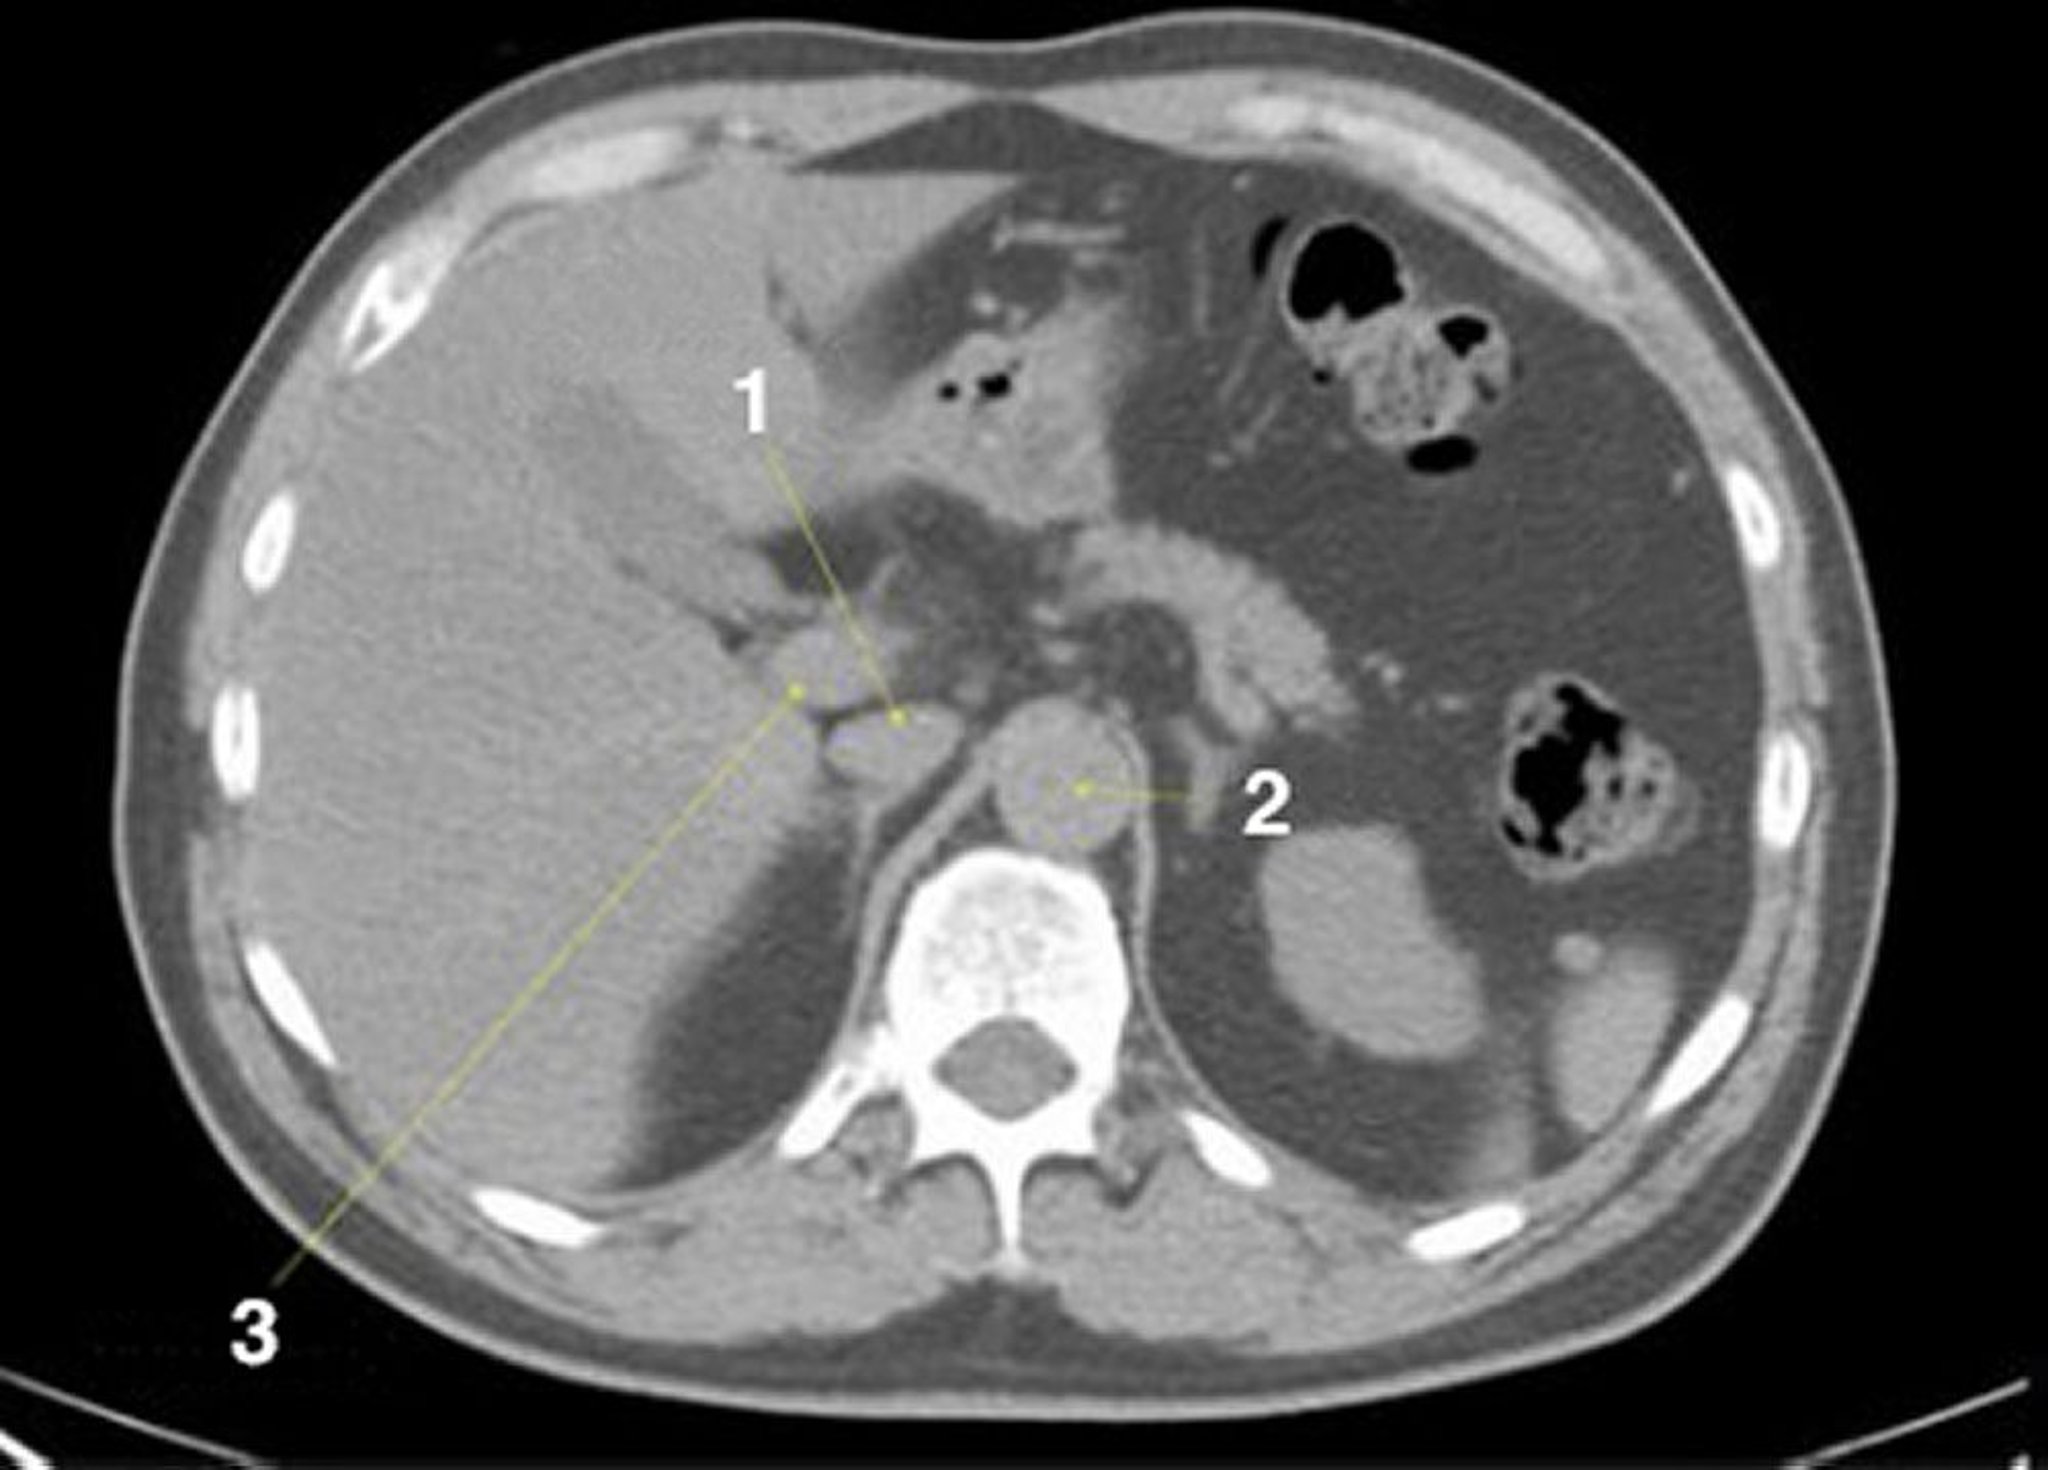

Noncontrast CT Scan of the Abdomen and Pelvis Showing Normal Anatomy (Slide 6)

1 = inferior vena cava; 2 = aorta; 3 = portal vein.